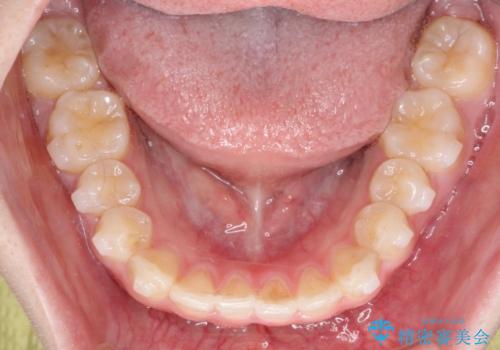

【インビザライン】前歯の凸凹をなおしたい

- 前歯のガタガタを主訴に来院されました。

インビザラインで綺麗な歯並びになり、患者さんには大変満足していただきました。

インビザラインは軽度叢生治療において優れた選択肢となります。